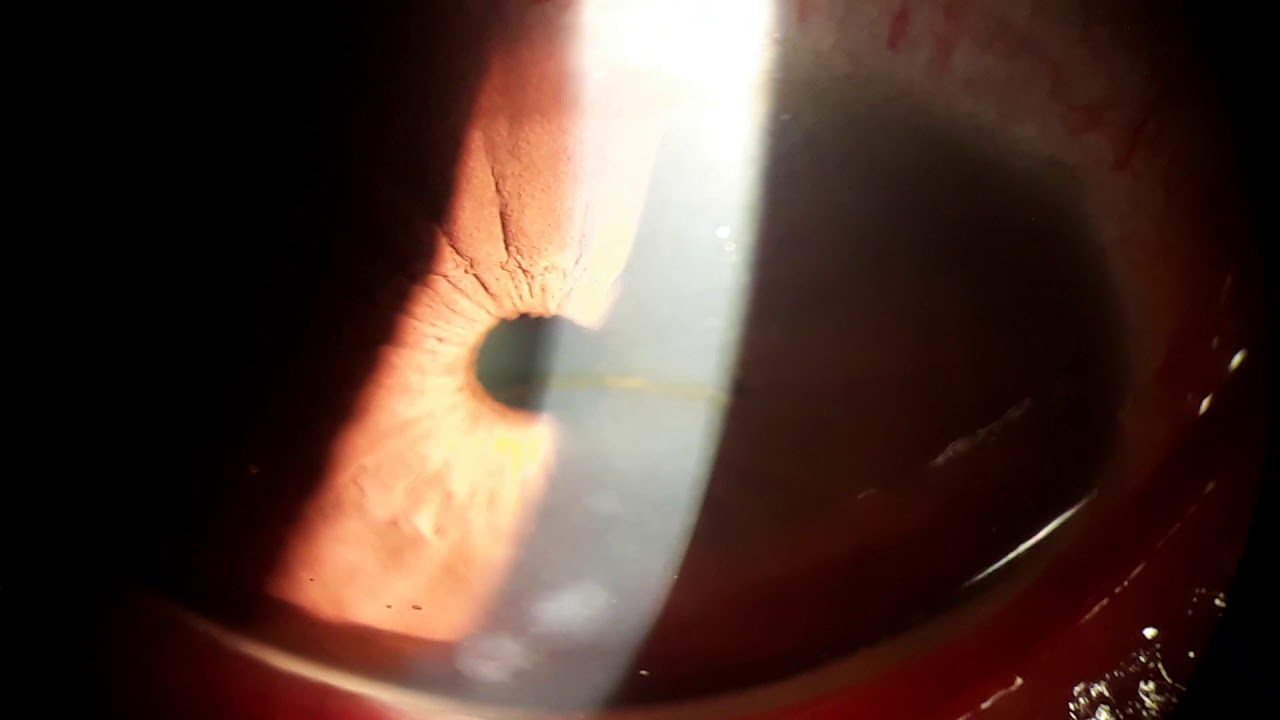

Vogt's Striae는 각막이 얇아지면서, 돌출되면서, 발생하는 기질의 긴장선, stress line 입니다.

데스메막 바로 앞쪽에 존재하는 각막 기질에 있는 여러개의 수직선입니다.

이는 각막이 흐물흐물해지면서 발생하게되는 선으로, 안압이 가해지면 사라집니다.

진단적으로 중요한 소견입니다..